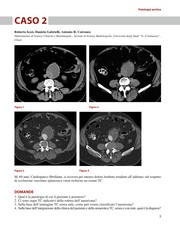

Imaging nelle urgenze vascolari — Body Casi clinici  Cover Image E-book E-book

Imaging nelle urgenze vascolari — Body Casi clinici